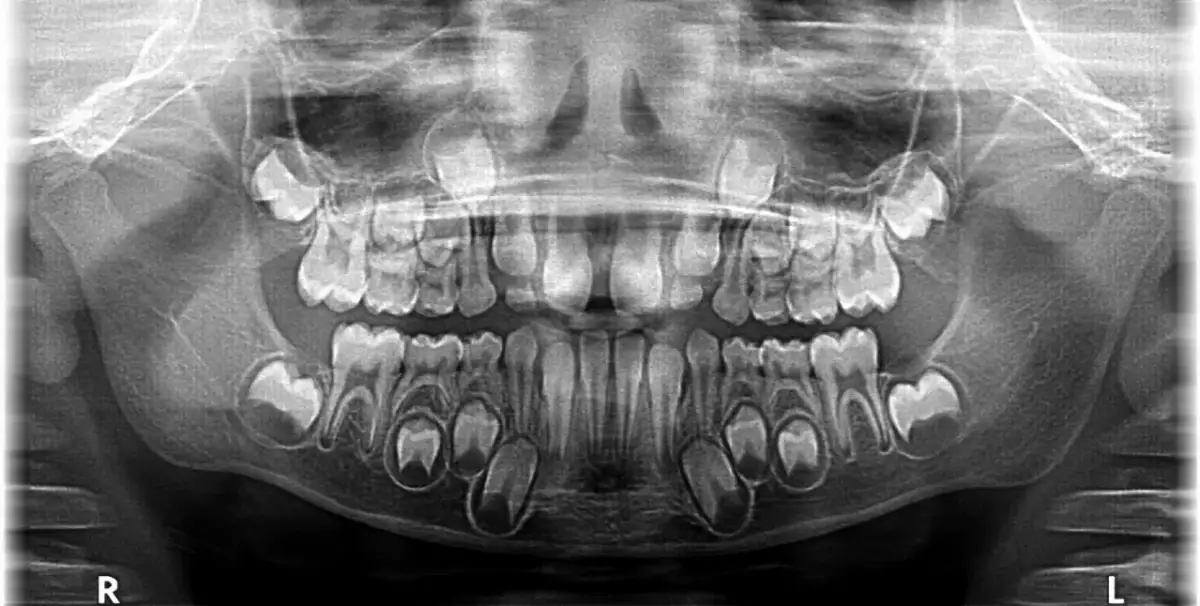

Uzębienie mieszane, czyli okres przejściowy pełen niespodzianek

Okres uzębienia mieszanego to fascynujący czas w rozwoju dziecka, kiedy w jego jamie ustnej współistnieją zarówno zęby mleczne, jak i stałe. Ten etap trwa od około 6. do 12-13. roku życia. To moment, w którym mleczaki stopniowo ustępują miejsca zębom stałym, co jest kluczowe dla prawidłowego rozwoju zgryzu i funkcji żucia. W tym czasie często obserwuję u dzieci dużą dynamikę zmian, a regularne wizyty u stomatologa są niezwykle ważne, aby monitorować ten proces.